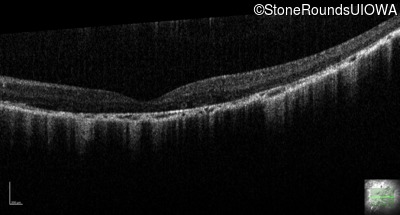

Optical Coherence Tomography - Right - 20/200 -2

Exemplar / OCT Stack

OCT Stack